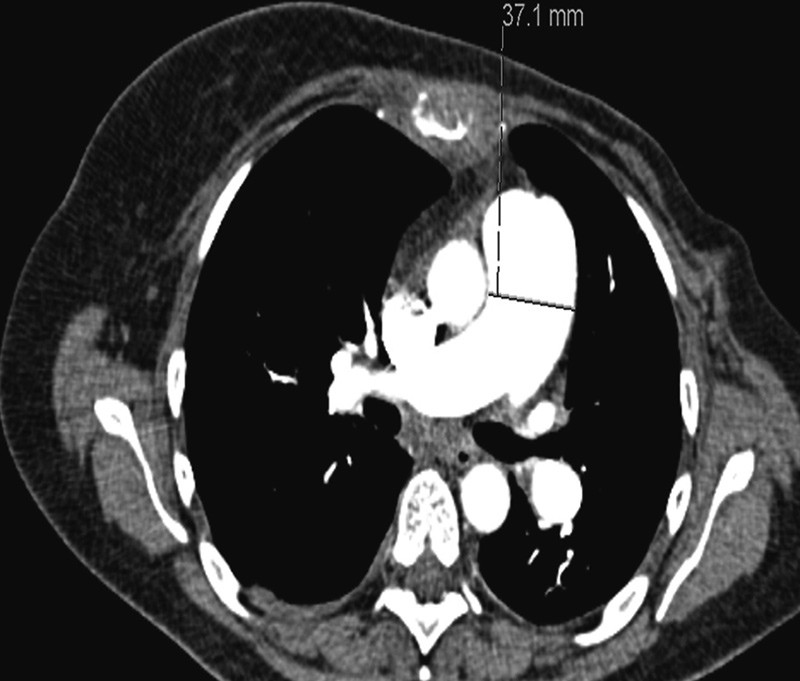

Pga. sykehistorie med dyspné og forhøyet D-dimer, mistenkte man lungeemboli. CT av lungearterier avdekket ikke lungeemboli (fig 1), men pga. mistanke om perifere lungeembolier, gikk man videre med lungescintigrafi.

Pga. fall i CRP (fra 123 mg/l til 103 mg/l) samt lett subjektiv bedring av symptomer ble pasienten i første omgang observert, uten behandling med antibiotika. CT av lungearterier var negativ for lungeembolier, men viste vid truncus pulmonalis (33 mm i motsetning til 27 mm ved foregående undersøkelse) som ga mistanke om pulmonal hypertensjon. For øvrig ble det påvist beskjeden vekst av metastaser.

CT thorax 16. innleggelsesdag viste ytterligere utvidet truncus pulmonalis, 37 mm (fig 2) samt tilkomne spredte, konsoliderende fortetninger i venstre lunges overlapp. Sammenliknet med tidligere EKG viste nytt EKG funn som ved høyrebelastning samt QR-mønster i V₁, negativ T i V2 og markert R-tap i fremreveggsavledningene. Pasienten ble henvist til ekko cor, som ble planlagt neste dag. Fra samme dag ble hun tiltakende takykard og hypotensiv og ble etter hvert overflyttet til lungepostens overvåkingsavdeling for respirasjonsstøtte med BiPAP. Morgenen 18. innleggelsesdag (ca. ti uker etter aller første innleggelse for dyspné) fikk pasienten plutselig respirasjonsstans og var ikke kontaktbar. Avansert hjerte-lunge-redning ble igangsatt, men uten at man lyktes i å gjenopprette egensirkulasjon. Pasienten ble erklært død ca. 30 minutter etter oppstart av resuscitering.